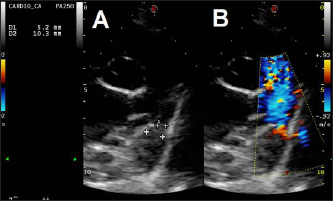

Fig. 4. Fluoroscopic sequence. (A) The first disc of the mVSD has been deployesd engaging the aortic side of the PDA and (B) then the waist and second disc fully extruded with the waist occluding the ostium and the second disc located into the pulmonary artery. (C) The stability of the device is tested with the push-pull “Minnesota wiggle” maneuver. (D) The device has been released

Fig. 5. Dual mode transthoracic echocardiography (right parasternal short axis view, optimized for duct visualization) 24 hours after surgery. The device discs (arrows) are correctly positioned and there is no evidence of residual shunt or pulmonary arterial obstruction given the laminar flow in the right pulmonary artery on CFM Doppler.

Echocardiographic checks at 3 and 24 hours showed complete PDA closure, correct positioning of the mVSDO (Fig. 5), and a clear reduction in left heart volume overload (LA: Ao decreased from 1.72 to 1.3, LVIDDN decreased from 2.49 to 2.43).